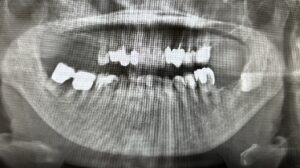

そもそもインプラントは失った歯を自分の歯の代わりとして人工の歯根を顎の骨に埋め込み、その上に人工の歯を装着して噛み合わせを回復する治療法です。

上の歯が難しいとされている大きな要因は下記の通りです。

【骨密度の問題】

・上顎は下顎に比べて骨密度が低い

・顎の骨に埋入した歯根部の結合に時間がかかる

・上記の理由から上の歯はインプラント治療が難しい

【副鼻腔の問題】

・顎の骨が薄いケース

・切歯管内の組織を巻き込まないように注意しなければならない

・インプラント周囲炎を起こすと上顎洞炎の原因になる